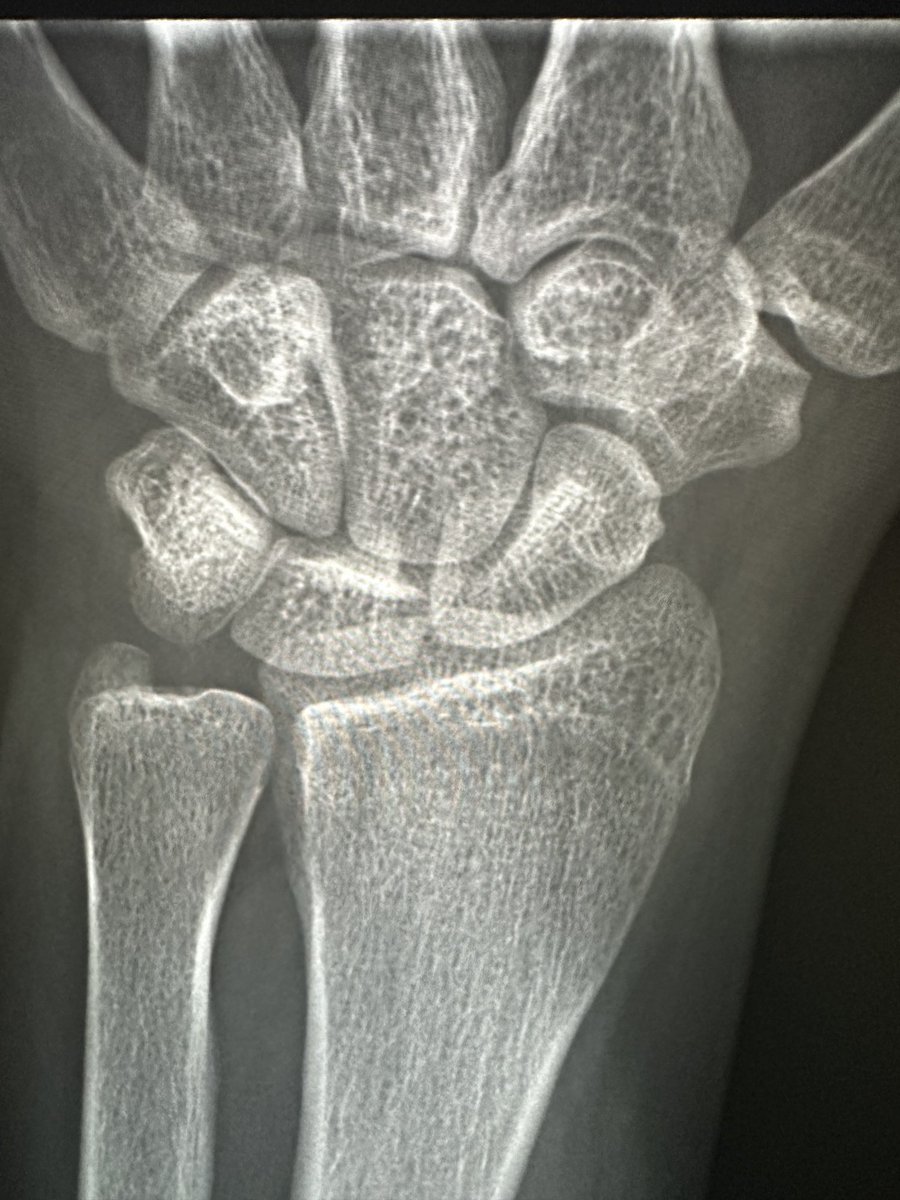

From twitter.com

RJ on Twitter "Young male. Flexion wrist injury. Persistent pain. Several nl radiographs. Call Wrist Injury Hyperflexion Here's what normal wrist flexion should be, how to tell if you have a problem, and exercises you can do today to improve your wrist flexion. We discuss the symptoms, causes and treatment options. Most sprains occur when the wrist is bent or twisted forcefully, such as in a fall onto. The inciting event typically involves the sudden application of. Wrist Injury Hyperflexion.